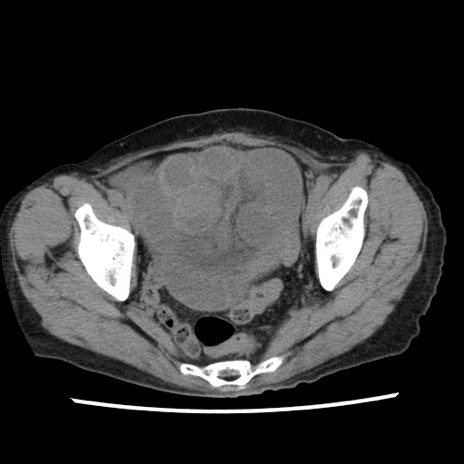

症例1(横断像)

【症例】80歳代女性

【主訴】腹痛

【現病歴】8時間前から腹痛あり来院。

【既往歴】糖尿病、脂質異常症、子宮体癌にて子宮全摘術

【身体所見】意識清明・会話良好だが腹痛で苦悶様、全腹部にわたって反跳痛と圧痛あり

【データ】WBC 13600、CRP 0.14、LDH 224、CK 90